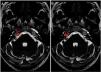

ResultsA total of 102 patients (63 women and 39 men) had vestibulocochlear involvement. The most common clinical indication was dizziness (41.18%). A unilateral vascular loop was found in 43 patients (right: 21.57%, left: 20.59%) and bilateral loops were found in 59 (57.84%) patients. The most common type of vascular loop was type II (right: 69.14%; left: 58.75%). The most common origin of vascular loops was the anterior inferior cerebellar artery (right: 66.67%, left: 65.00%). No associations were observed between vascular loops and sensorineural hearing, nystagmus, or vertigo. There was an association with tinnitus.

Resultados102 pacientes (63 mujeres y 39 hombres) presentaban afectación vestibulococlear. La indicación clínica más frecuente fue mareos (41,18%). Se halló asa vascular unilateral en 43 pacientes (derecho: 21,57%, izquierdo: 20,59%) y bilateral en 59 pacientes (57,84%). El tipo de asa vascular más frecuente fue el tipo II (derecho: 69,14%; izquierdo: 58,75%). El origen más frecuente fue la arteria cerebelosa anteroinferior (ACAI) (derecha: 66,67%, izquierda: 65,00%). No se observó ninguna asociación entre asas vasculares y pérdida de audición neurosensitiva, nistagmo o vértigo. Se halló una asociación con acúfenos.